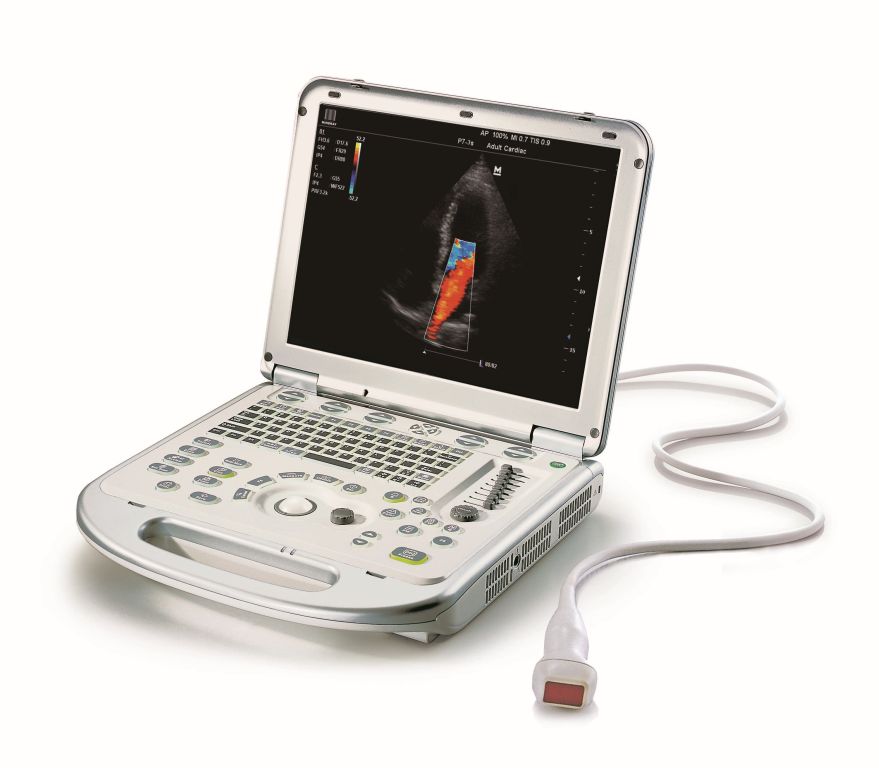

Mindray M7/M6 je dopplerovský ultra ľahký prenosný UZV prístroj strednej triedy s použitím HD sond. Stress echo. 4D. TDI. Panoramatické zobrazenie...

- Pulzný, Spektrálny Doppler (PW), citlivý Farebný Doppler (CFM), ultracitlivý smerový Power Doppler (PDI), anatomický - M mód a Stress Echo

- 15“ High resolution LCD monitor / 320 GB HDD/ hmotnosť 6,5 kg